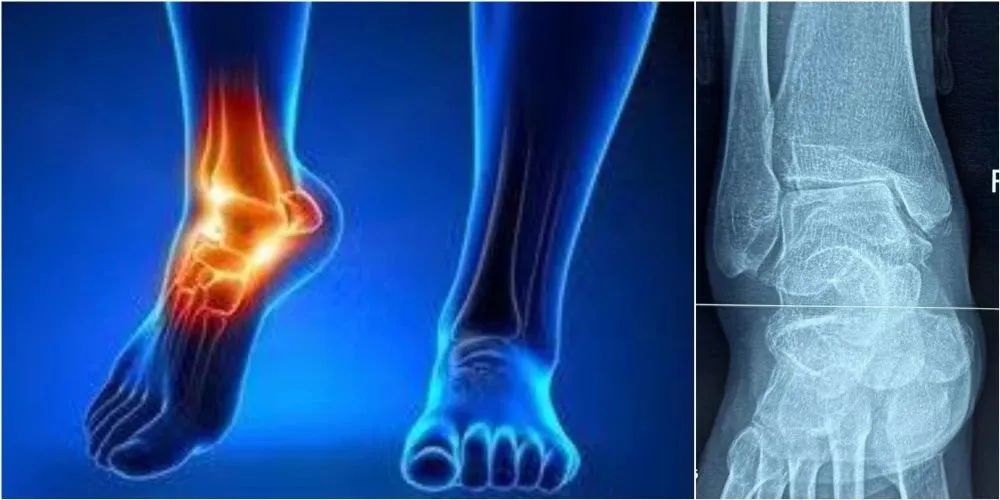

(六)踝关节炎

踝关节是马拉松运动过程中下肢主要的承重关节,如果长跑姿势不正常,非常容易导致损伤,常见的足踝部损伤包括:骨损伤、软骨损伤、韧带损伤、肌腱损伤、软组织损伤等。踝关节炎也是一种常见的病症,其中创伤性踝关节炎最为常见。

关节内骨折和严重的踝关节扭伤是最常见的创伤机制之一,由此引发的踝关节不协调,力线排列不齐和关节脱位是导致发生踝关节创伤性关节炎的主要因素。踝关节炎的患者常表现为关节僵硬、肿胀、关节活动度减小、局部炎症,随着活动量的增加疼痛剧烈,严重者出现跛行等症状。早期诊断有助于早期对病程的干预,其诊断主要依赖患者的临床表现和影像学检查,包括X线、CT及核磁等检查。